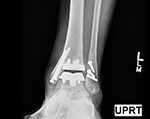

Ankle Joint replacement has dramatically improved the treatment of ankle arthritis over the past decade leading to decreased pain and an improvement in function.

The development of patient-specific technology has further enhanced the accuracy of implant alignment and decreased the surgical time.